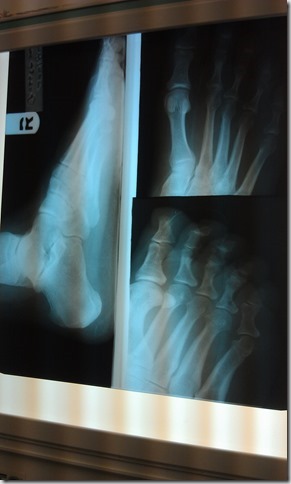

I went to a different podiatrist on Tuesday. The part just below the pinky toe is swollen from an unknown injury. I was given a cortisone shot. Later that evening, it was nice not to have foot pain for a change.